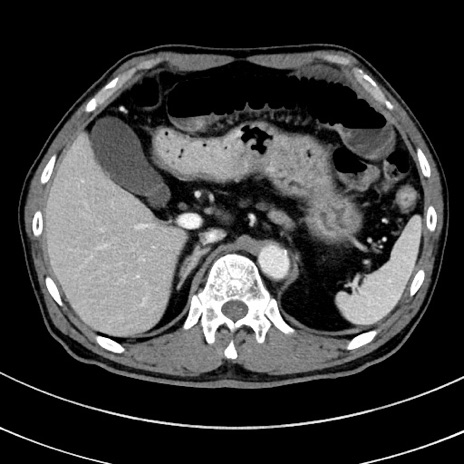

冠状断像

【症例】 60歳代男性

【主訴】 黒色吐物

【現病歴】 4日前から嘔気自覚、2日前の朝食後にも嘔気あり、自分で手で嘔吐反射起こし嘔吐したところ血が混ざっていたため受診。

【既往歴】 5年前汎発性腹膜炎を伴う急性虫垂炎で手術、高血圧、前立腺肥大症、高脂血症

【身体所見】 腹部正中に手術癩痕あり 腹部平坦・軟圧痛なし膨満感あり

【データ】WBC 8400、CRP 4.54